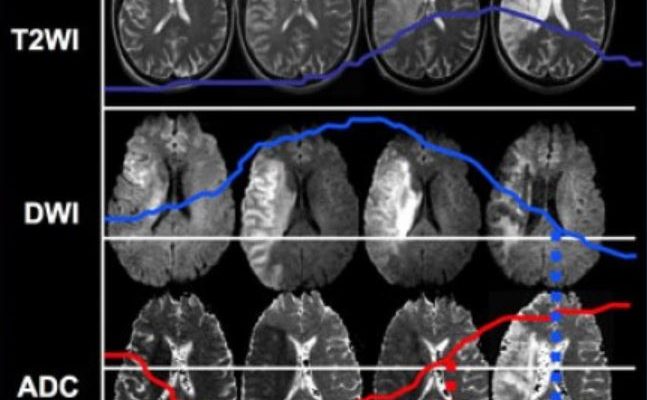

Искусственный Интеллект на Страже Здоровья: Как Мы Сегментируем Опухоли на МРТ-снимках Медицинская визуализация – это невероятно важная область современной медицины.

ИИ в медицине: Как мы научили компьютер видеть воспаление на МРТ В современном мире искусственный интеллект (ИИ) проникает во все сферы нашей жизни, и

ИИ на страже здоровья: Как мы научили компьютер видеть воспаление на МРТ Приветствуем вас, дорогие читатели! Сегодня мы хотим поделиться с вами захватывающей

Искусственный Интеллект на Страже Здоровья: Наш Опыт Разработки ИИ для Анализа МРТ В современном мире технологии проникают во все сферы нашей жизни, и